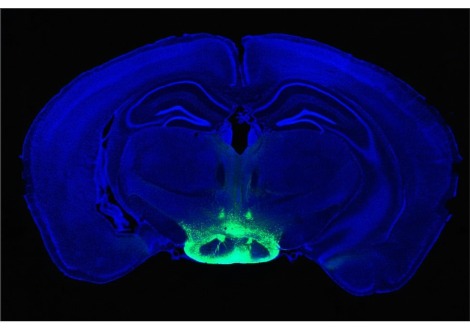

دفعت مثل هذه الاختلافات باحث الألم فرانك بوريكا من جامعة أريزونا للعلوم الصحية في توكسون وزملائه إلى دراسة الخلايا العصبية التي تسمى مستقبلات الألم، والتي يمكن أن تعمل مثل أجهزة استشعار إنذار للجسم. يمكن لمستشعرات الألم الموجودة في الخلايا، الموجودة في الجلد والأعضاء وأماكن أخرى في الجسم، اكتشاف المحفزات التي يحتمل أن تكون خطرة وإرسال إشارات إلى الدماغ، الذي يفسر بعد ذلك المعلومات على أنها ألم. في بعض الحالات، يمكن أن تصبح الخلايا العصبية أكثر حساسية للتحفيز الخارجي، وتسجل حتى الأحاسيس اللطيفة - مثل فرك القميص على الجلد المصاب بحروق الشمس - كألم.

باستخدام أنسجة من الفئران والقرود والبشر، درس الباحثون آثار مادتين يمكنهما حساسية الخلايا العصبية للألم: هرمون يسمى البرولاكتين وناقل عصبي يسمى أوريكسين B. عندما تكتشف الخلايا العصبية هذه المواد، تصبح أكثر حساسية للمنبهات. ، مما يخفض العتبة التي ترسل عندها الخلايا إشارات كهربائية إلى الدماغ للإشارة إلى وجود خطأ ما. في جميع الأنواع الثلاثة، أدى التعرض للبرولاكتين إلى جعل الخلايا العصبية لدى الإناث أكثر نشاطًا، في حين كان للأوركسين B تأثير مماثل على تلك الموجودة لدى الذكور.